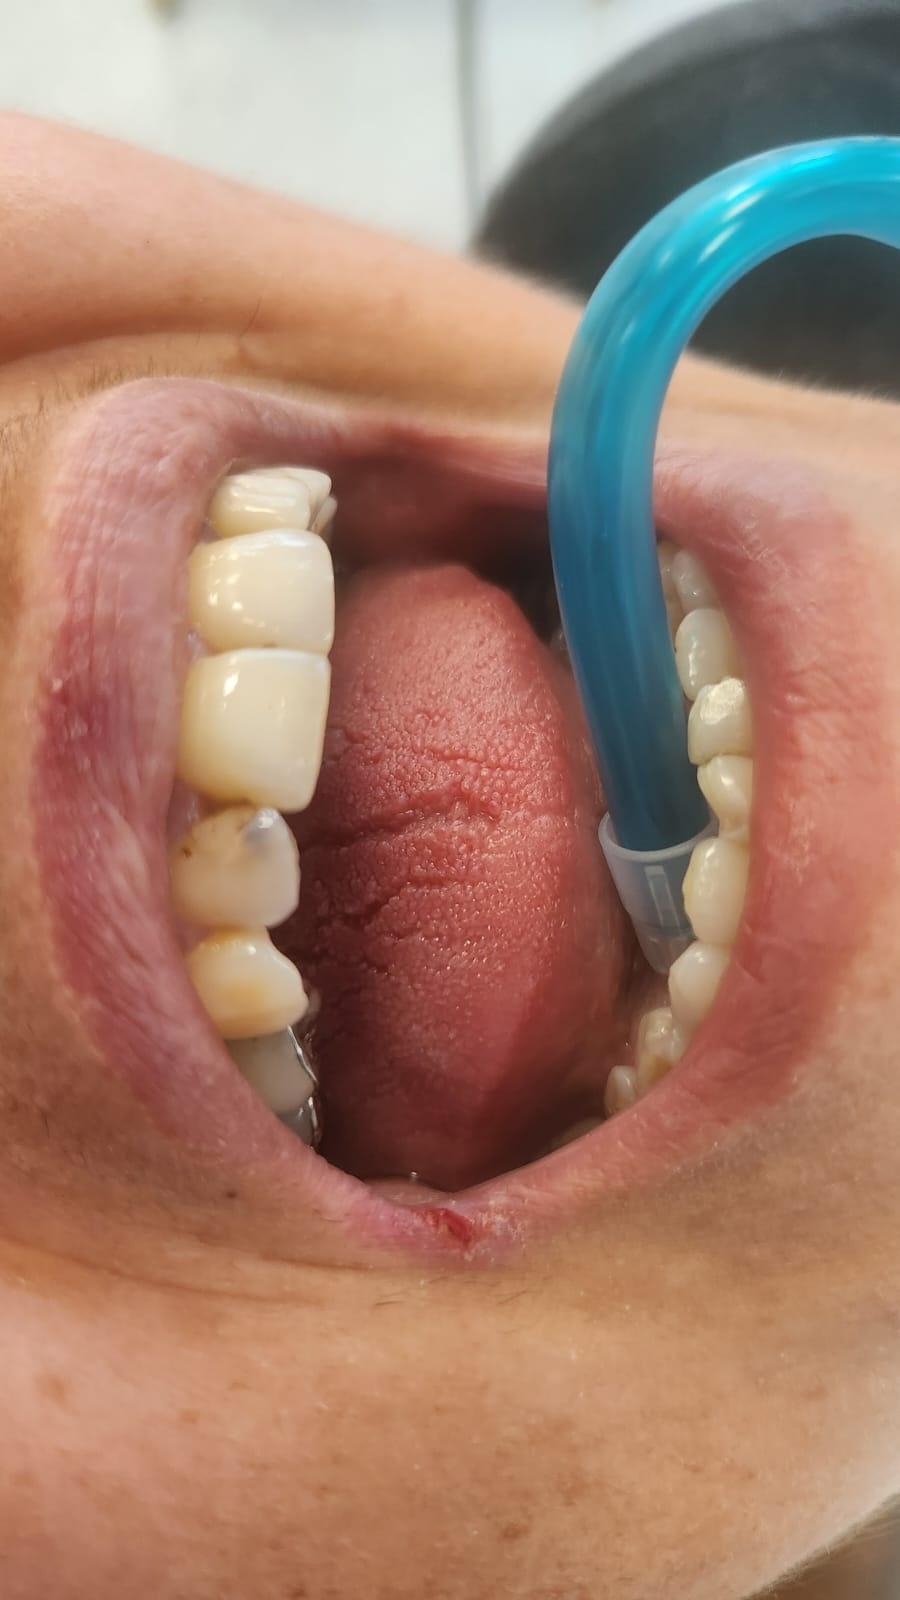

O igiena riguroasa a cavitatii bucale, presupune folosirea urmatoarelor:

– un periaj corect;

– ata dentara si apa de gura;

– periuta interdentara;

– folosirea dusului bucal.

Recomandam controale periodice (3-6 luni) pentru igienizari profesionale: detartraj, periaj dentar, air-flow etc. Aceste operatiuni asigura sanatatea gingiei, iar osul alveolar si ligamentele parodontale isi pastreaza integritatea.